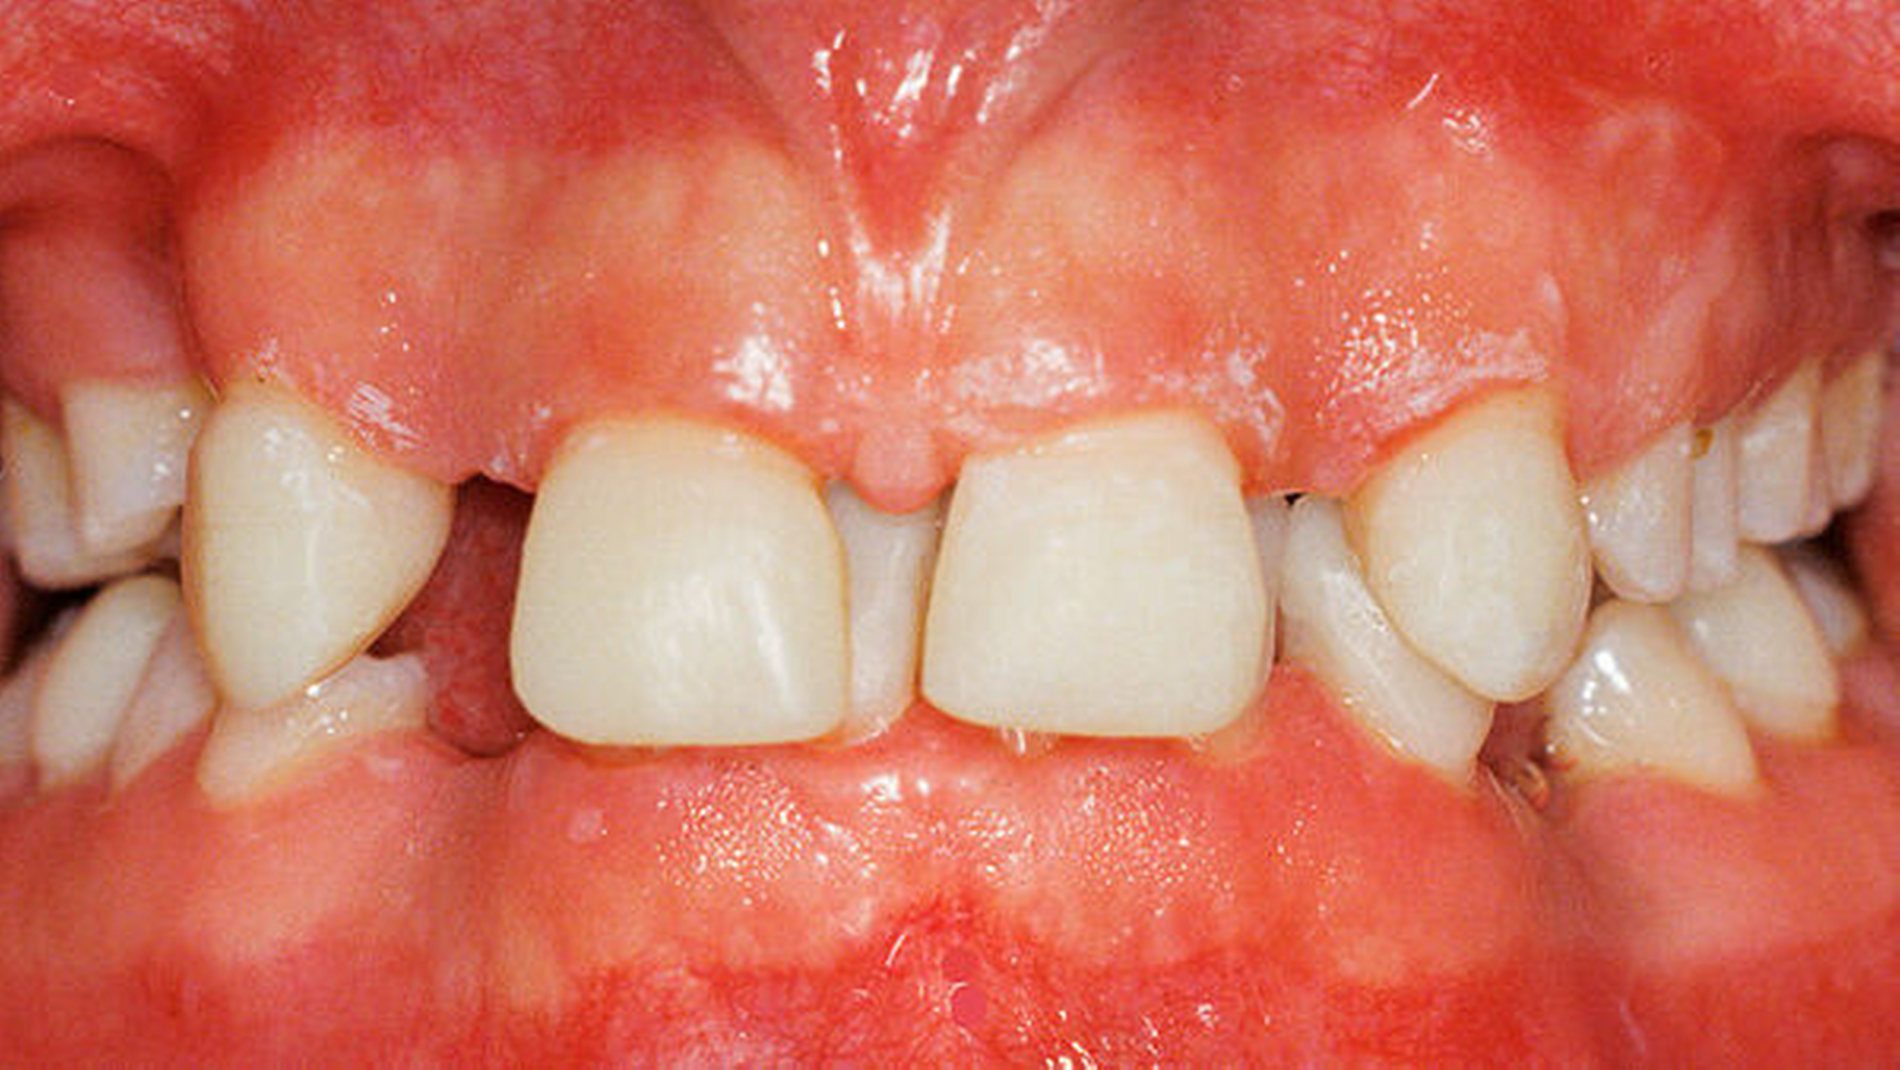

Die 16-jährige Patientin war unglücklich über ihre lückig stehenden Zähne und wünschte eine Verbesserung der durch die Dysgnathie beeinträchtigten Kaufunktion und ihres Aussehens (Porträtbilder en face und seitlich Abbildungen 1a und 1b, enorale Situation Abbildungen 2a bis 2c).

Anhand des klinischen Befunds, des Orthopantomogramms (Abbildung 3), der Durchzeichnung des seitlichen Fernröntgenbildes (Abbildung 4) und der Analyse der einartikulierten Modelle wurden folgende Diagnosen gestellt: skelettale und dentale Klasse II nach Angle (Distalbiss), Tiefbiss, Aplasie der Zähne 12, 14, 22, 34, 42, Persistenz und Infraposition der Zähne 54 und 74, Mikrodontie, starke Attrition der Oberkiefer- und der Unterkiefer-Front- und Eckzähne.